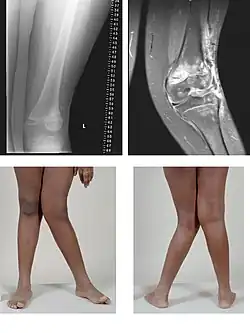

| A very severe case of genu valgum of the left knee following bone cancer treatment | |

Genu valgum, commonly called "knock-knee", is a condition in which the knees angle in and touch each other when the legs are straightened.[1] Individuals with severe valgus deformities are typically unable to touch their feet together while simultaneously straightening the legs. The term originates from Latin genu 'knee' and valgus 'bent outwards', but is also used to describe the distal portion of the knee joint which bends outwards and thus the proximal portion seems to be bent inwards.